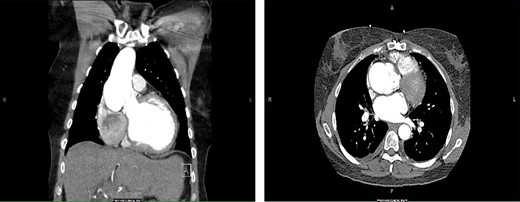

A 56-year-old female presented to the emergency department with chest tightness and shortness of breath for 2 days. The patient had a history of a Ross procedure for aortic insufficiency associated with a bicuspid aortic valve 16 years previously. A computed tomography (CT) scan at the time of admission revealed a 6.1-cm aneurysm with a small dissection flap (Fig. 1). The patient had recently undergone an echocardiogram that revealed a preserved ejection fraction of 55–60% and aortic root dilation to 5.9 cm with additional dilation of the ascending aorta to 4.4 cm. As echocardiography just 6 months earlier had measured the aortic root and ascending aorta at 5 and 3.8 cm, respectively, concern had been raised for accelerated aneurysmal degeneration and planning for elective aneurysm repair had been underway. Given the patient’s symptomatic presentation and associated CT findings, she was admitted for medical optimization and was taken to the operating room 8 days later.

CT of the chest. Coronal (left) and axial (right) views demonstrating pathologic dilatation of the aortic root and ascending aorta. On the axial image, a dissection plane is noted in the aortic root.